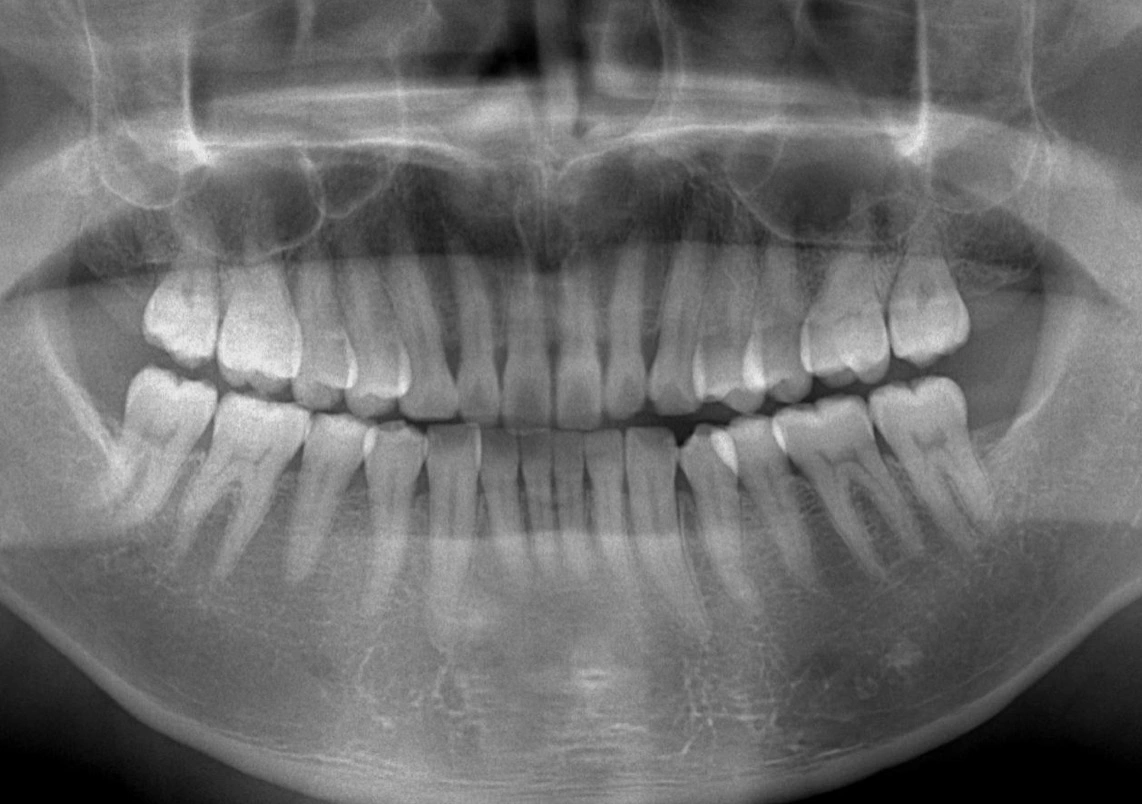

虫歯は虫歯菌が出す「酸」により、少しづつ歯が溶かされていく症状です。歯の表面はエナメル質に覆われているので、その進行は比較的ゆっくりです。この段階での虫歯は歯の中心にある神経から遠いので痛み等の自覚症状は現れません。

歯が「しみる」「痛む」等、トラブルを感じるようになるには、既に虫歯がそこまで進行してしまっているということなのです。放っておくとダメージが増え、治療が複雑になってきます。虫歯は早期発見・早期治療が大事です。また当院は、虫歯の予防に力を入れており、ご家庭でのブラッシング方法などをご指導しております。お気軽にご相談ください。

日本人成人の8割が歯周病ないしは歯周病予備軍と言われております。歯周病は痛みなどの自覚症状があまりない疾患ですので静かに進行していく病気です。「歯茎が腫れている」「歯茎から血が出る」などの症状がある方はもちろん、自覚症状のない方もお気軽にご相談ください。歯周病からお口の健康を守ることは、全身の健康を守ることになります。

歯列・咬合の異常は、いろいろな障害を引き起こします。

咀嚼障害(咀嚼能力の低下)、審美障害、構音障害、顎発育障害などのほかにも、う蝕、歯周病、顎関節症、外傷などの原因にもなります。

日常生活に影響する場合もあるため、お早めにご相談ください。

軽度のものは矯正治療、補綴治療で治します。高度の場合には外科的に骨切り術が適応されます。矯正が必要な場合は、専門医と連携して治療にあたります。